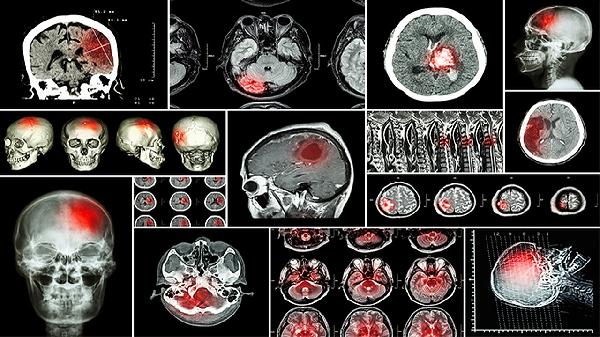

该药通过水牛角浓缩粉与麝香等成分促进血脑屏障通透性,改善脑部微循环。适用于中风急性期出现的言语不利、意识模糊,或一氧化碳中毒导致的意识障碍。合并脑水肿患者需配合脱水剂使用。

所含胆红素具有抗氧化特性,能减少自由基对脑细胞的损伤。可用于颅脑外伤后遗症的记忆力减退,或脑血管痉挛引起的头痛头晕。肝肾功能不全患者应减量使用。